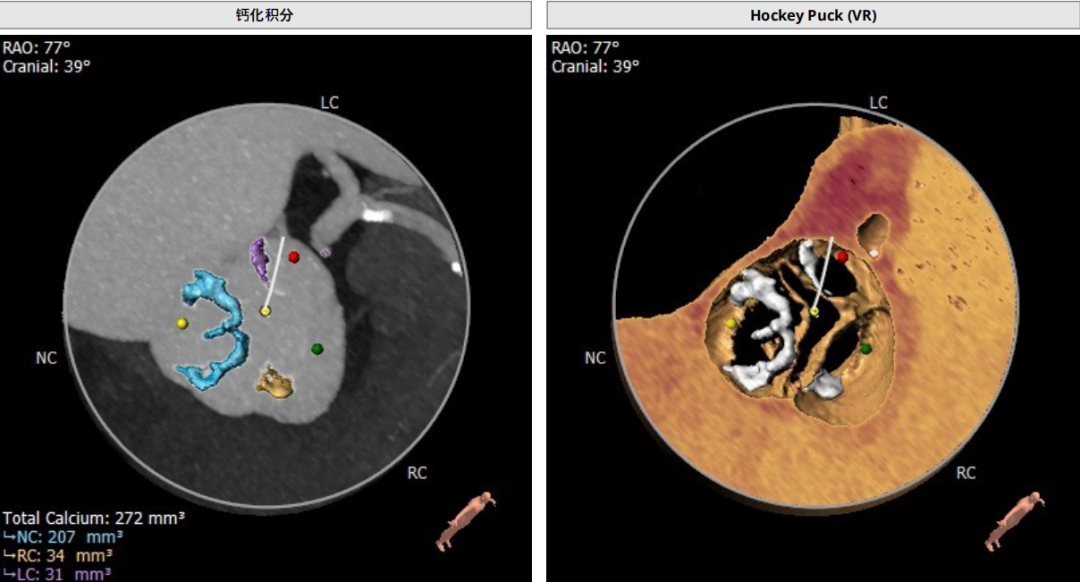

钙化积分:272

手术策略

患者主动脉瓣呈功能性型二叶瓣,轻度钙化,法式窦结构不大,双冠高度可,升主动脉未见明显增宽,心脏角度约47°,心肌肥厚,主动脉弓部走形平缓。

选用23mm球囊进行预扩张,通过造影观察,主动脉瓣重度狭窄,预期病人耐受球囊扩张后的反流。考虑瓣环25.2mm的直径、左室流出道25.5mm的直径、钙化分布等因素,因此判断瓣环结构对瓣膜位置要求极高,有较高风险发生瓣周漏,通过FEops技术进行综合评估后,考虑选用L29型号瓣膜,并采取稍高位释放。